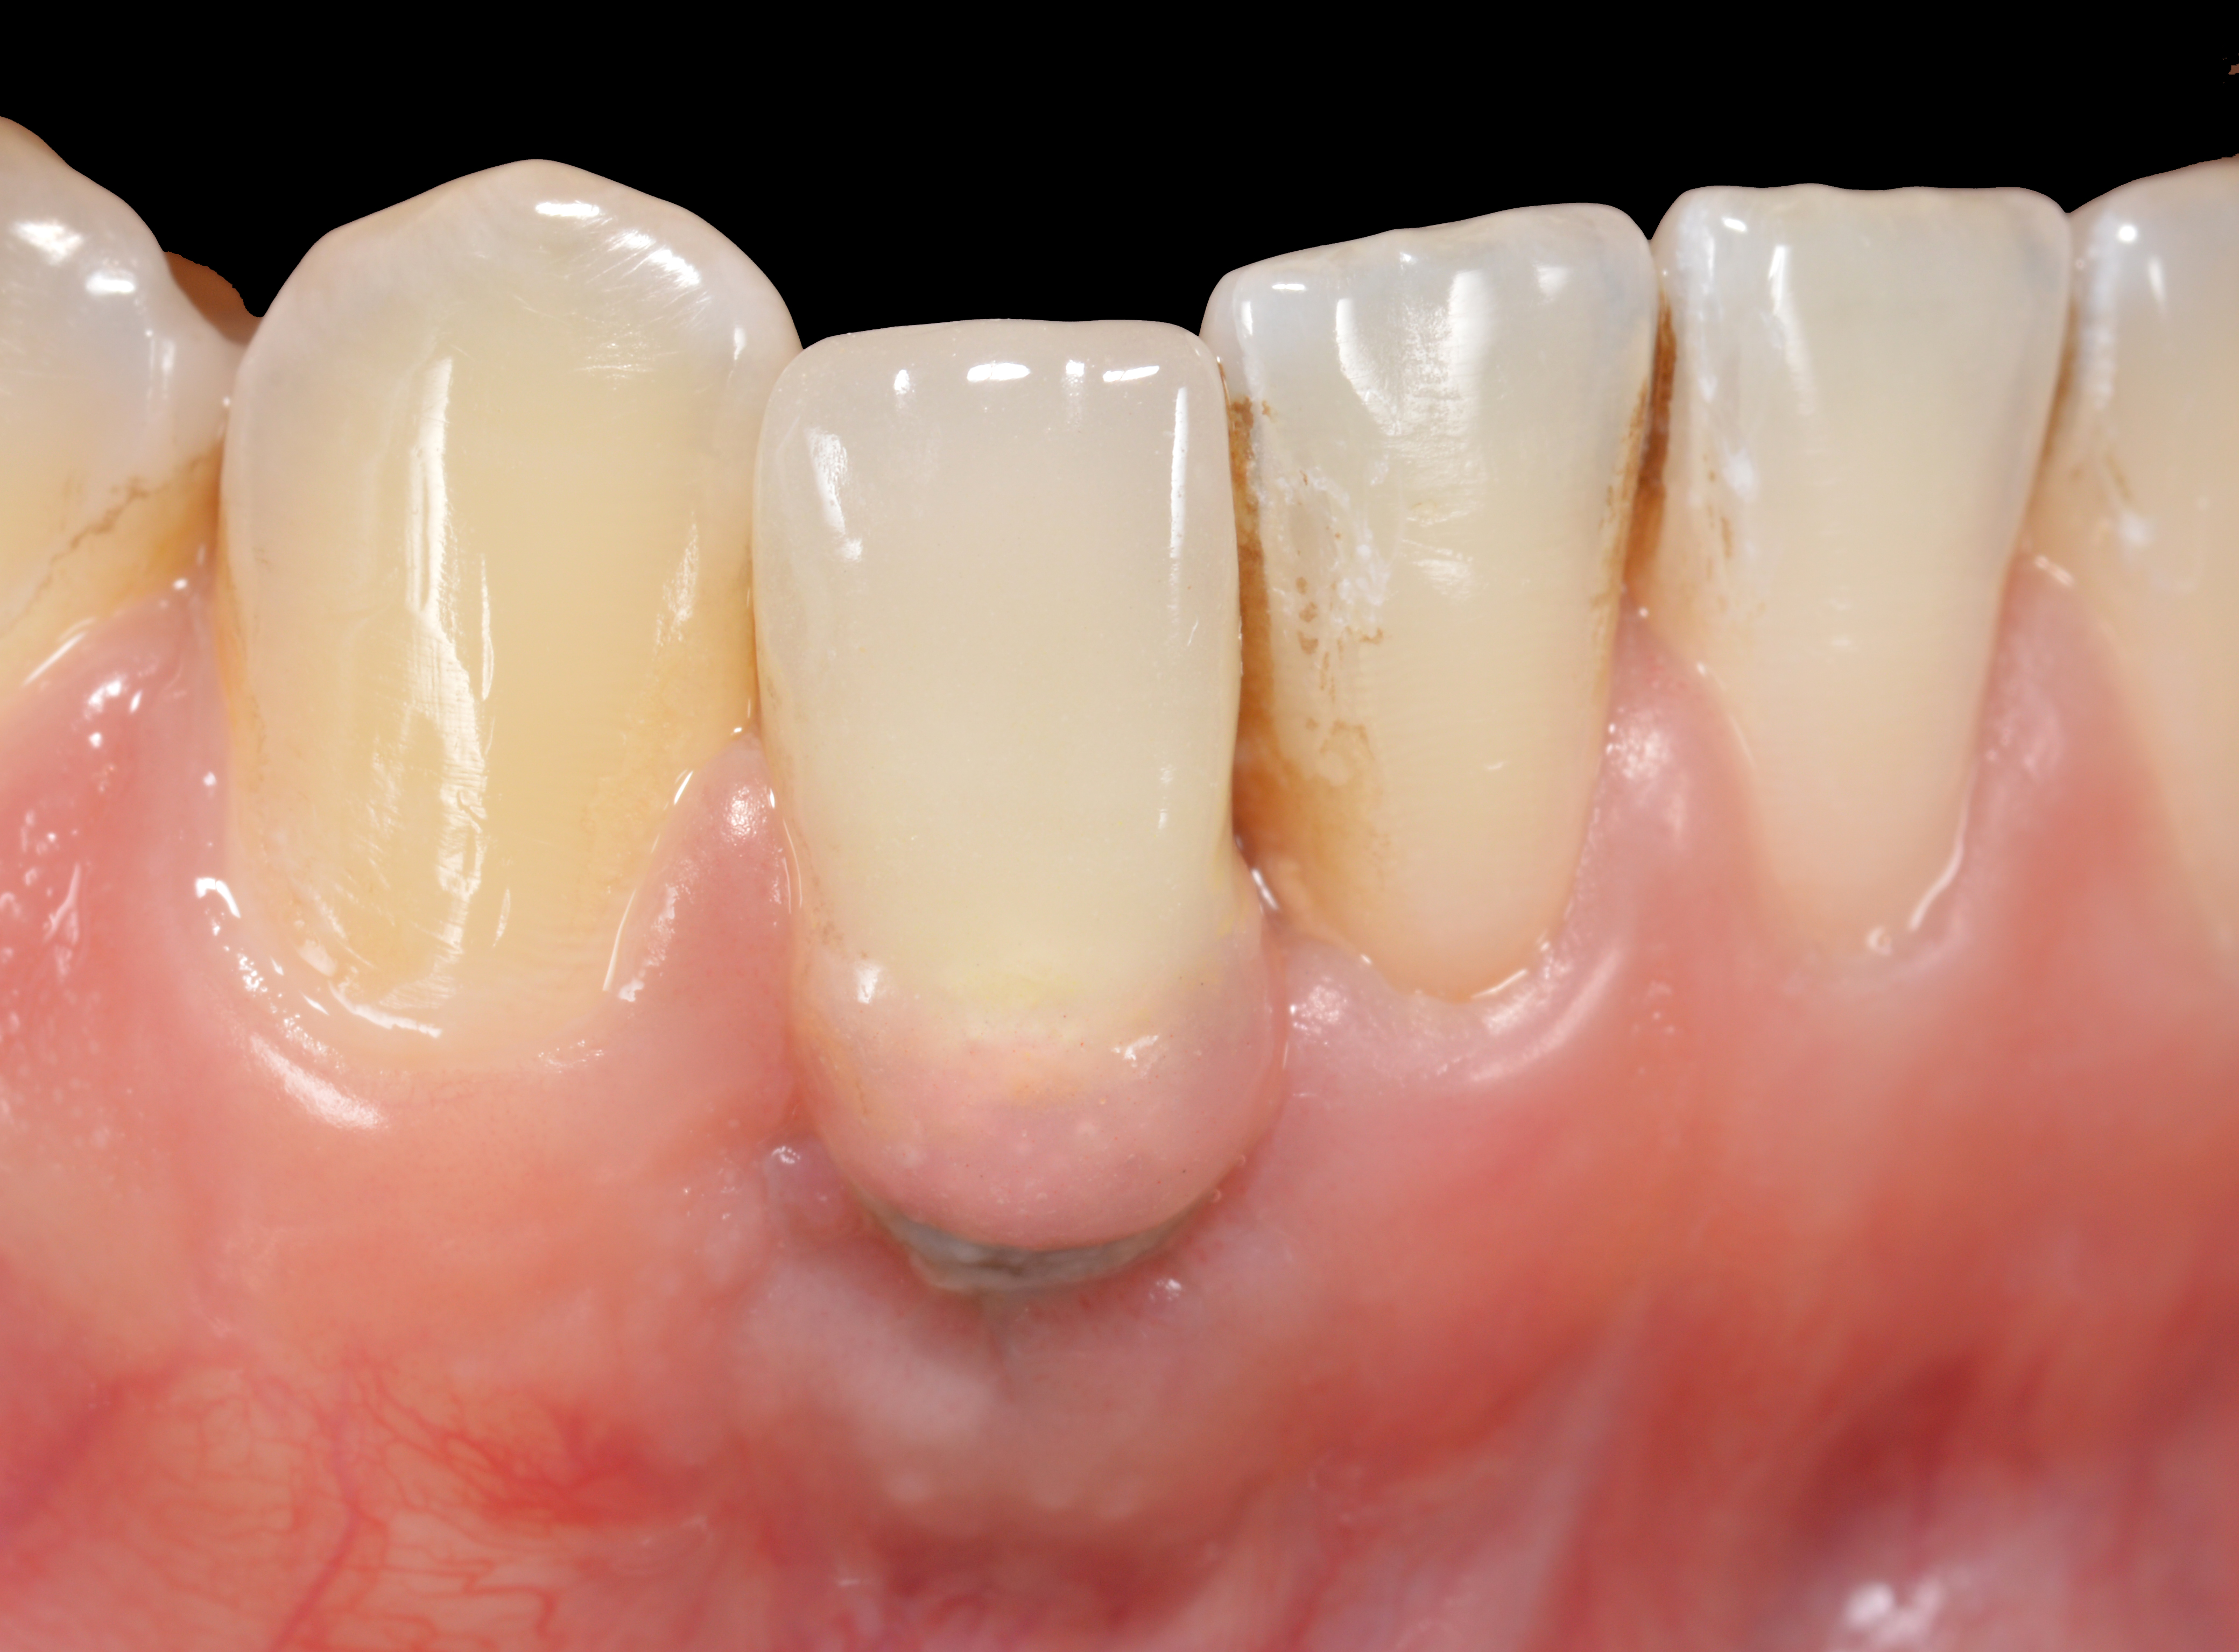

Fig 45. The definitive crown tooth No. 26 seated in place and provisionally cemented. The recession defect was eliminated with the removal and replacement of a new implant in the proper position.

Figure 45

Fig 46. The post-treatment radiograph showing a healthy stable implant and restoration.

Figure 46